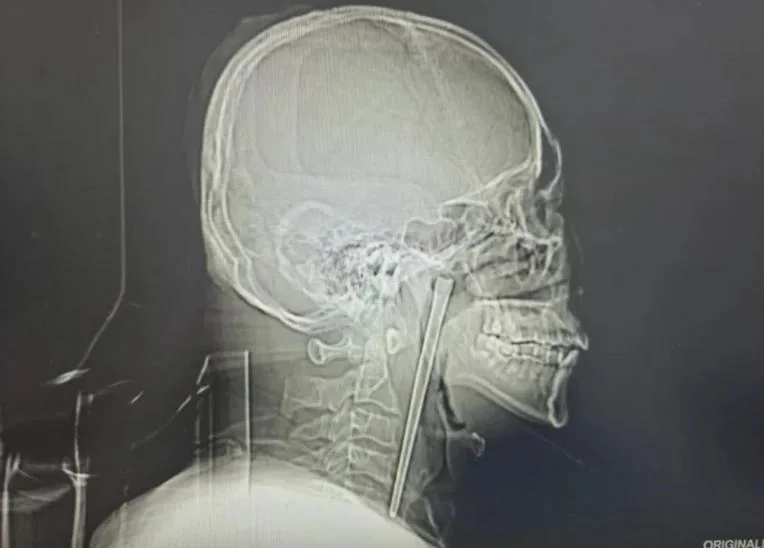

ทีมแพทย์ช็อกภาพเอกซเรย์ แท่งโลหะยาว 12 ซม. ติดอยู่ในลำคอคนไข้มานาน 8 ปี!

ทีมแพทย์ช็อกภาพเอกซเรย์ แท่งโลหะยาว 12 ซม. ติดอยู่ในลำคอคนไข้มานาน 8 ปี เล่าย้อนเหตุการณ์ ยิ่งฟังยิ่งอึ้ง

กลายเป็นเรื่องฮือฮาในโลกโซเชียลจีน เมื่อนายหวัง ชายวัย 46 ปี จากเมืองต้าเหลียน มณฑลเหลียวหนิง เข้ารับการรักษาที่แผนกโสต ศอ นาสิก ลาริงซ์ และศัลยกรรมศีรษะและคอ โรงพยาบาลศูนย์ในสังกัดมหาวิทยาลัยเทคโนโลยีต้าเหลียน (Dalian University of Technology Hospital) ด้วยอาการปวดคออย่างรุนแรงและรู้สึกเหมือนมีสิ่งแปลกปลอมติดคอจนทนไม่ไหว แต่ผลการตรวจกลับทำให้คณะแพทย์ต้องตกตะลึง เมื่อพบตะเกียบโลหะยาวถึง 12 เซนติเมตร ฝังอยู่ในลำคอของเขามานานถึง 8 ปี

นพ. หวง เว่ยเผิง แพทย์ผู้ดูแลเคสนี้ได้ทำการตรวจร่างกายและใช้กล้องส่องตรวจกล่องเสียงระบบอิเล็กทรอนิกส์ (Electronic Laryngoscopy) พบว่ามีตะเกียบโลหะฝังอยู่ใต้ผนังเยื่อบุลำคอด้านหลังทางขวาและหลังเพดานอ่อน โดยส่วนที่มองเห็นด้วยตาเปล่ามีความยาวประมาณ 3 เซนติเมตร อย่างไรก็ตาม ทีมแพทย์พบข่าวดีว่าเยื่อบุลำคอโดยรอบไม่มีการแตกหัก เลือดออก หรือเป็นหนอง และสายเสียงยังทำงานได้ปกติ